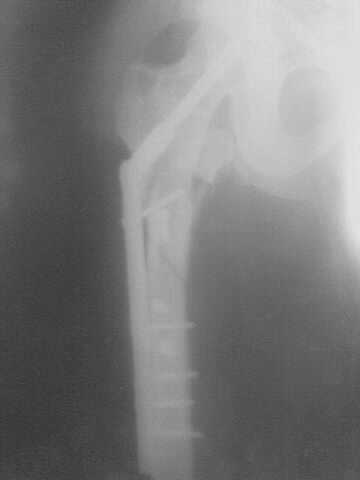

Я тоже считаю, сперва необходимо разобраться с переломаной и

деформированой вертлужной впадиной, одномоментно устравнить вывих

головки бедренной кости, с фиксацией диафиза (чем там у Вас есть), а

остальное после активной подготовки больного. С уважением А.Леспович